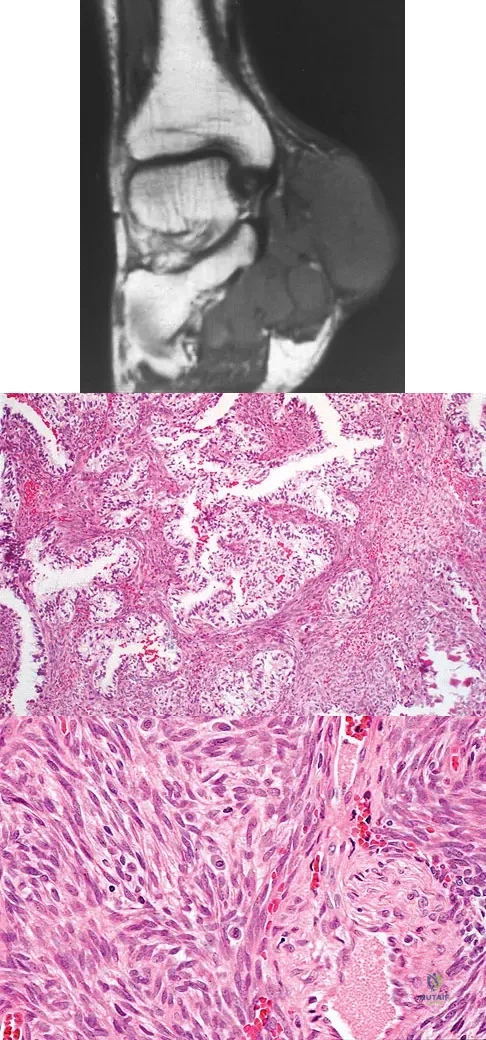

A 40-year-old man has a painless mass around his left ankle. He notes minimal growth over the past year. An MRI scan is shown in Figure 73a, and biopsy specimens are shown in Figures 73b and 73c. What is the most likely diagnosis?

Explanation:

The biopsy specimen is a low-power view of a soft-tissue sarcoma with a biphasic pattern of epithelial cells and fibrous spindle cells that are typical of a synovial sarcoma. A deep, painless soft-tissue mass greater than 5 cm in size is suspicious for a sarcoma. The imaging in this patient is indeterminate and the patient requires a biopsy for an accurate diagnosis. The biopsy reveals a tumor with a biphasic appearance consistent with a synovial sarcoma. These tumors are slow growing, occur primarily in the lower extremities, and are found in a younger demographic population compared to malignant fibrous histiocytoma and liposarcoma. They can occur in a biphasic pattern with clumps of epithelial cells and fibrous spindle cells or in a monophasic pattern. Synovial sarcomas stain positively for keratin. Keratin is positive in nearly all biphasic types and in many tumors of the monophasic fibrous type. Sixty percent of these tumors are found in the lower extremity. The area around the knee is the most common location, followed by the ankle and foot. Epithelioid and clear cell sarcomas are found associated with tendon sheaths of the hand and feet and are generally smaller in size. Epithelioid sarcoma may resemble granulomatous inflammation histologically; clear cell sarcoma is composed of nests of clear cells with occasional multinucleated giant cells. Pigmented villonodular synovitis is found within the synovium and is characterized by a villous histologic appearance with hemosiderin-laden macrophages. Malignant fibrous histiocytoma has a storiform histologic pattern with an abundance of pleomorphic cells. Enzinger FM, Weiss SW: Soft Tissue Tumors, ed 3. St Louis, MO, Mosby, 1995, p 757.